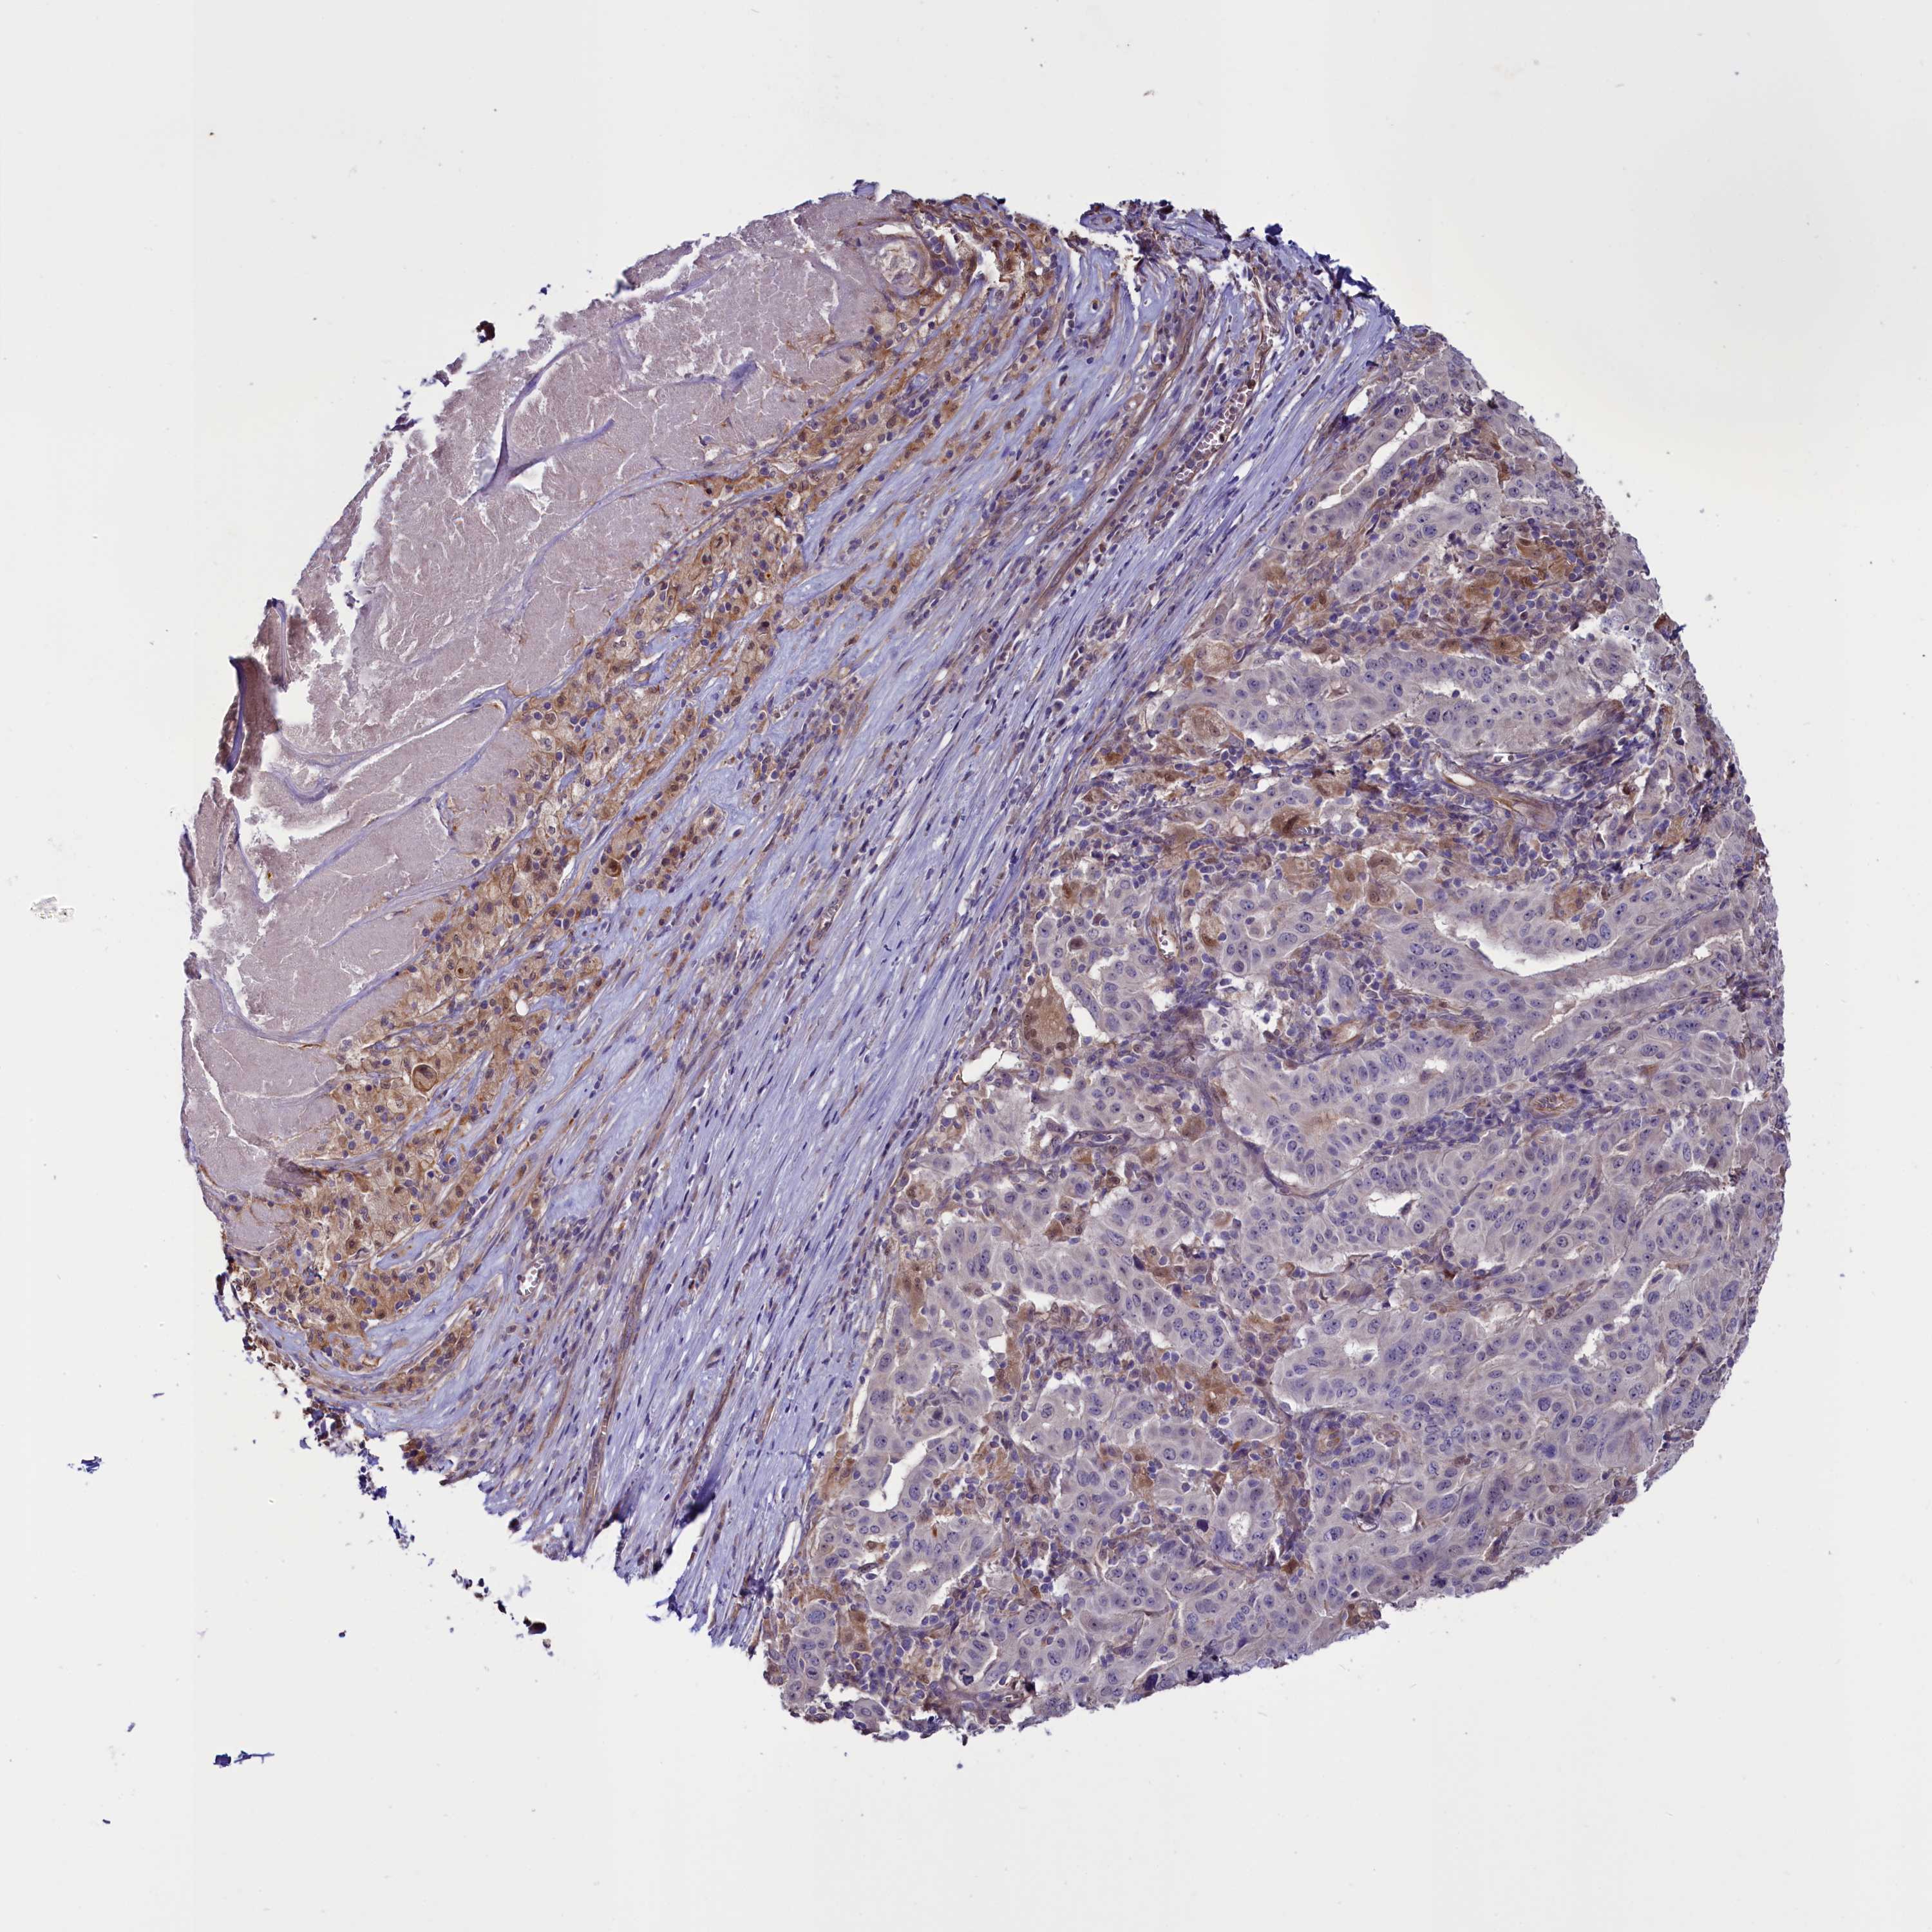

PANCREATIC CANCER - Protein expressioni

A mouse-over function shows sample information and annotation data. Click on an image to view it in a full screen mode. Samples can be filtered based on level of antibody staining by selecting one or several of the following categories: high, medium, low and not detected. The assay and annotation is described here.

Note that samples used for immunohistochemistry by the Human Protein Atlas do not correspond to samples in the TCGA dataset.

Antibody stainingi

Antibody staining in the annotated cell types in the current human tissue is reported as not detected, low, medium, or high, based on conventional immunohistochemistry profiling in selected tissues. This score is based on the combination of the staining intensity and fraction of stained cells.

Each image is clickable and will lead to virtual microscopy that enables deeper exploration of all samples and also displays staining intensity scores, fraction scores and subcellular localization as well as patient and tissue information for each sample.

Antibody HPA041913

Staining

High

Medium

Low

Not detected

Intensity

Strong

Moderate

Weak

Negative

Quantity

>75%

75%-25%

<25%

None

Location

Nuclear

Cytoplasmic/membranous

Cytoplasmic/membranous,nuclear

Adenocarcinoma, NOS